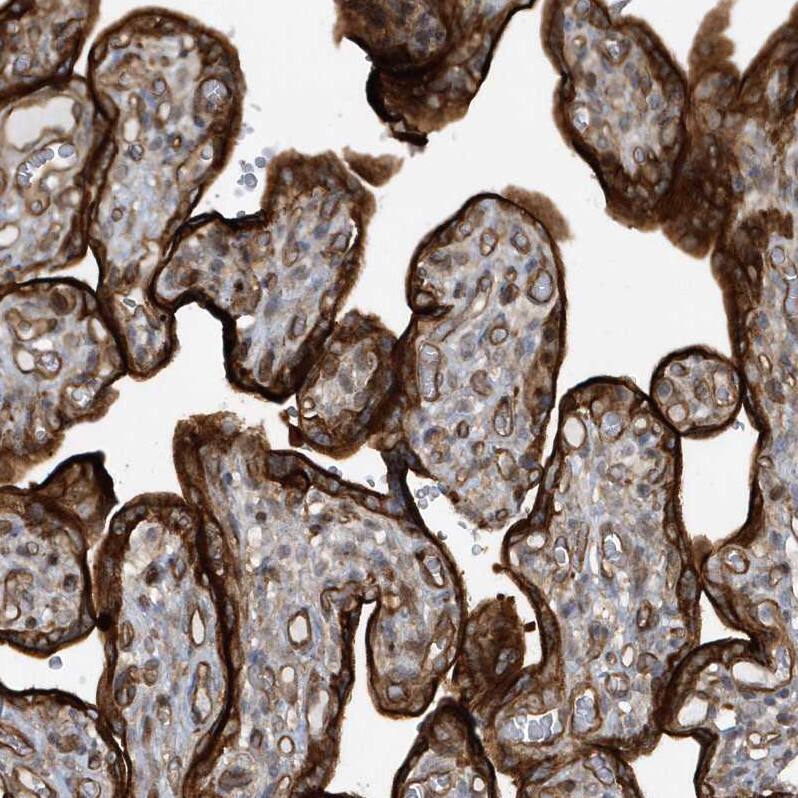

Immunohistochemistry-Paraffin: RAI14 Antibody [NBP1-94075] - Staining of human placenta shows strong cytoplasmic and membranous positivity in trophoblastic cells.Western Blot: RAI14 Antibody - BSA Free [NBP1-94075]